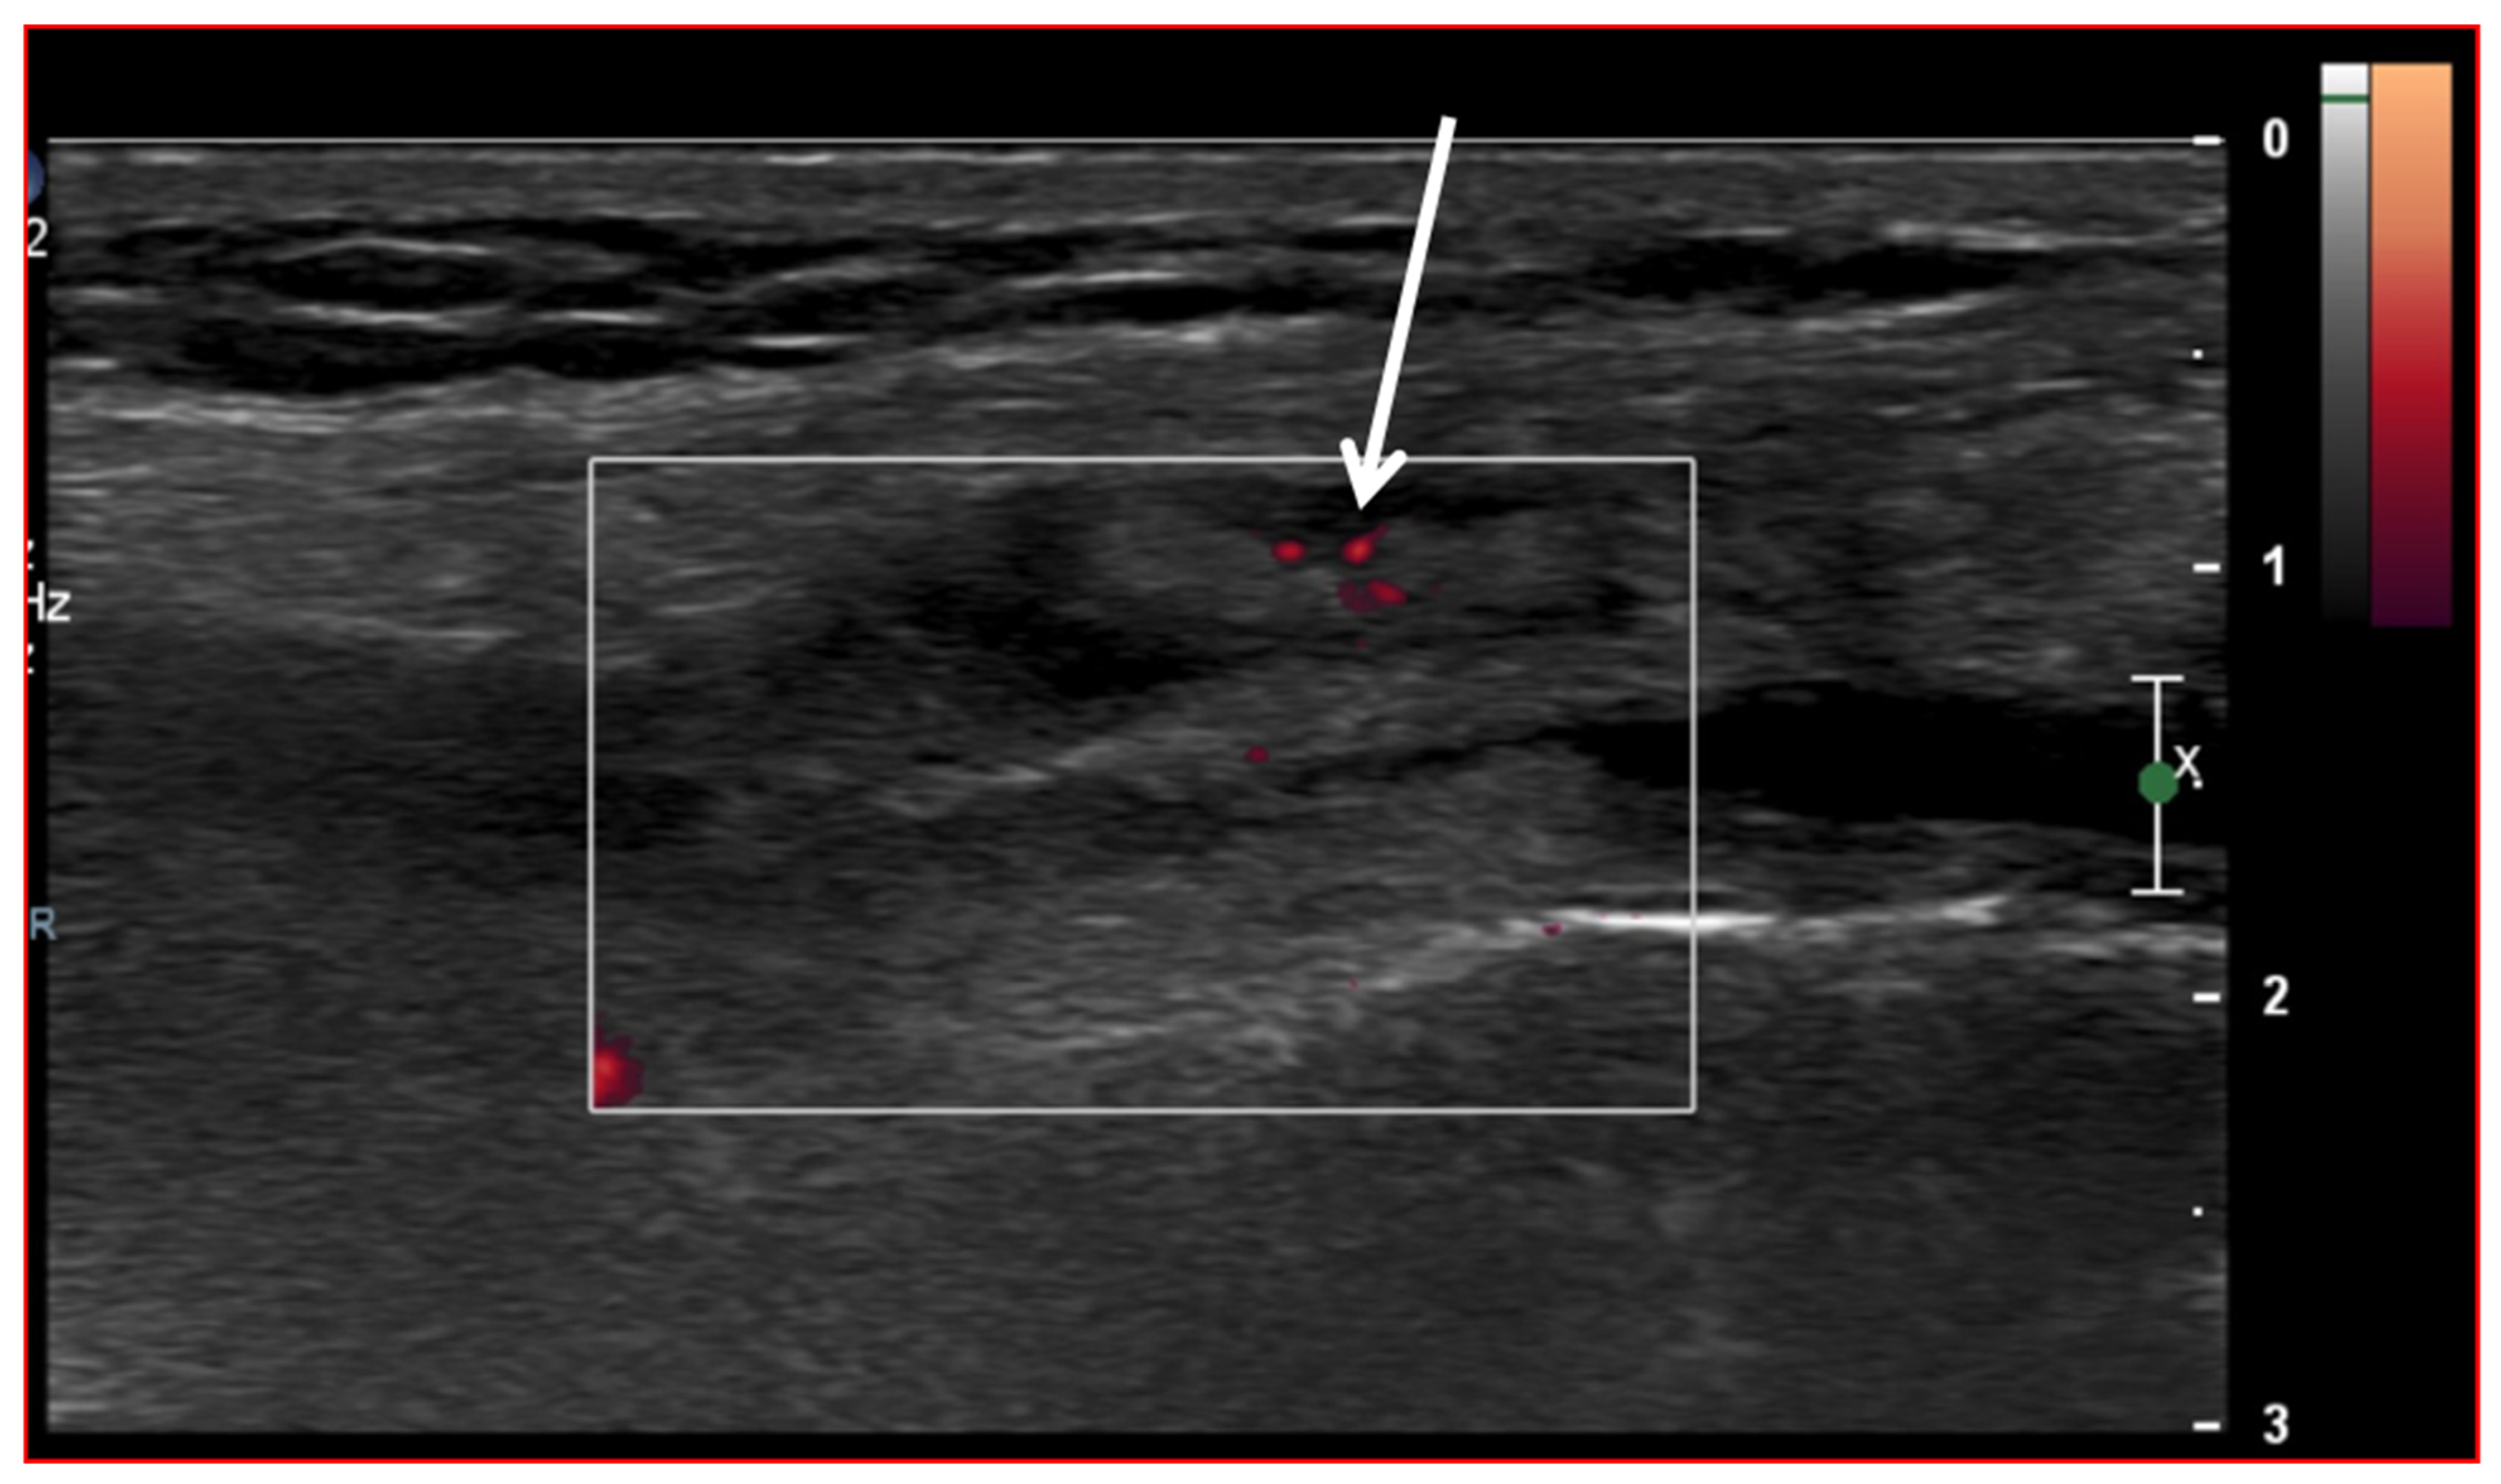

Ultrasound (US) imaging has not traditionally been used as part of the clinical pipeline for OA diagnostics. However, when examining the scientific literature, its role has risen steadily during the last two decades. US assessment of joints offers several advantages, including the ability to assess soft-tissue changes associated with OA and to outline the contour of the bony surface surrounding the joint [64,65]. In addition to detecting structural OA changes, a US can provide insights into inflammatory findings, complementing traditional CR imaging [66]. Several inflammatory findings (e.g., joint effusion/Baker cyst, synovial thickening, and hyper-vascularity), easily detectable throughout a US, are associated with pain exacerbation and disease progression in knee OA (Figure 2, Figure 3 and Figure 4).

Figure 3.

Ultrasound image (Power-Doppler) longitudinal, lateral suprapatellar view showing synovial inflammatory foci with inflammatory hyperemia (arrow).